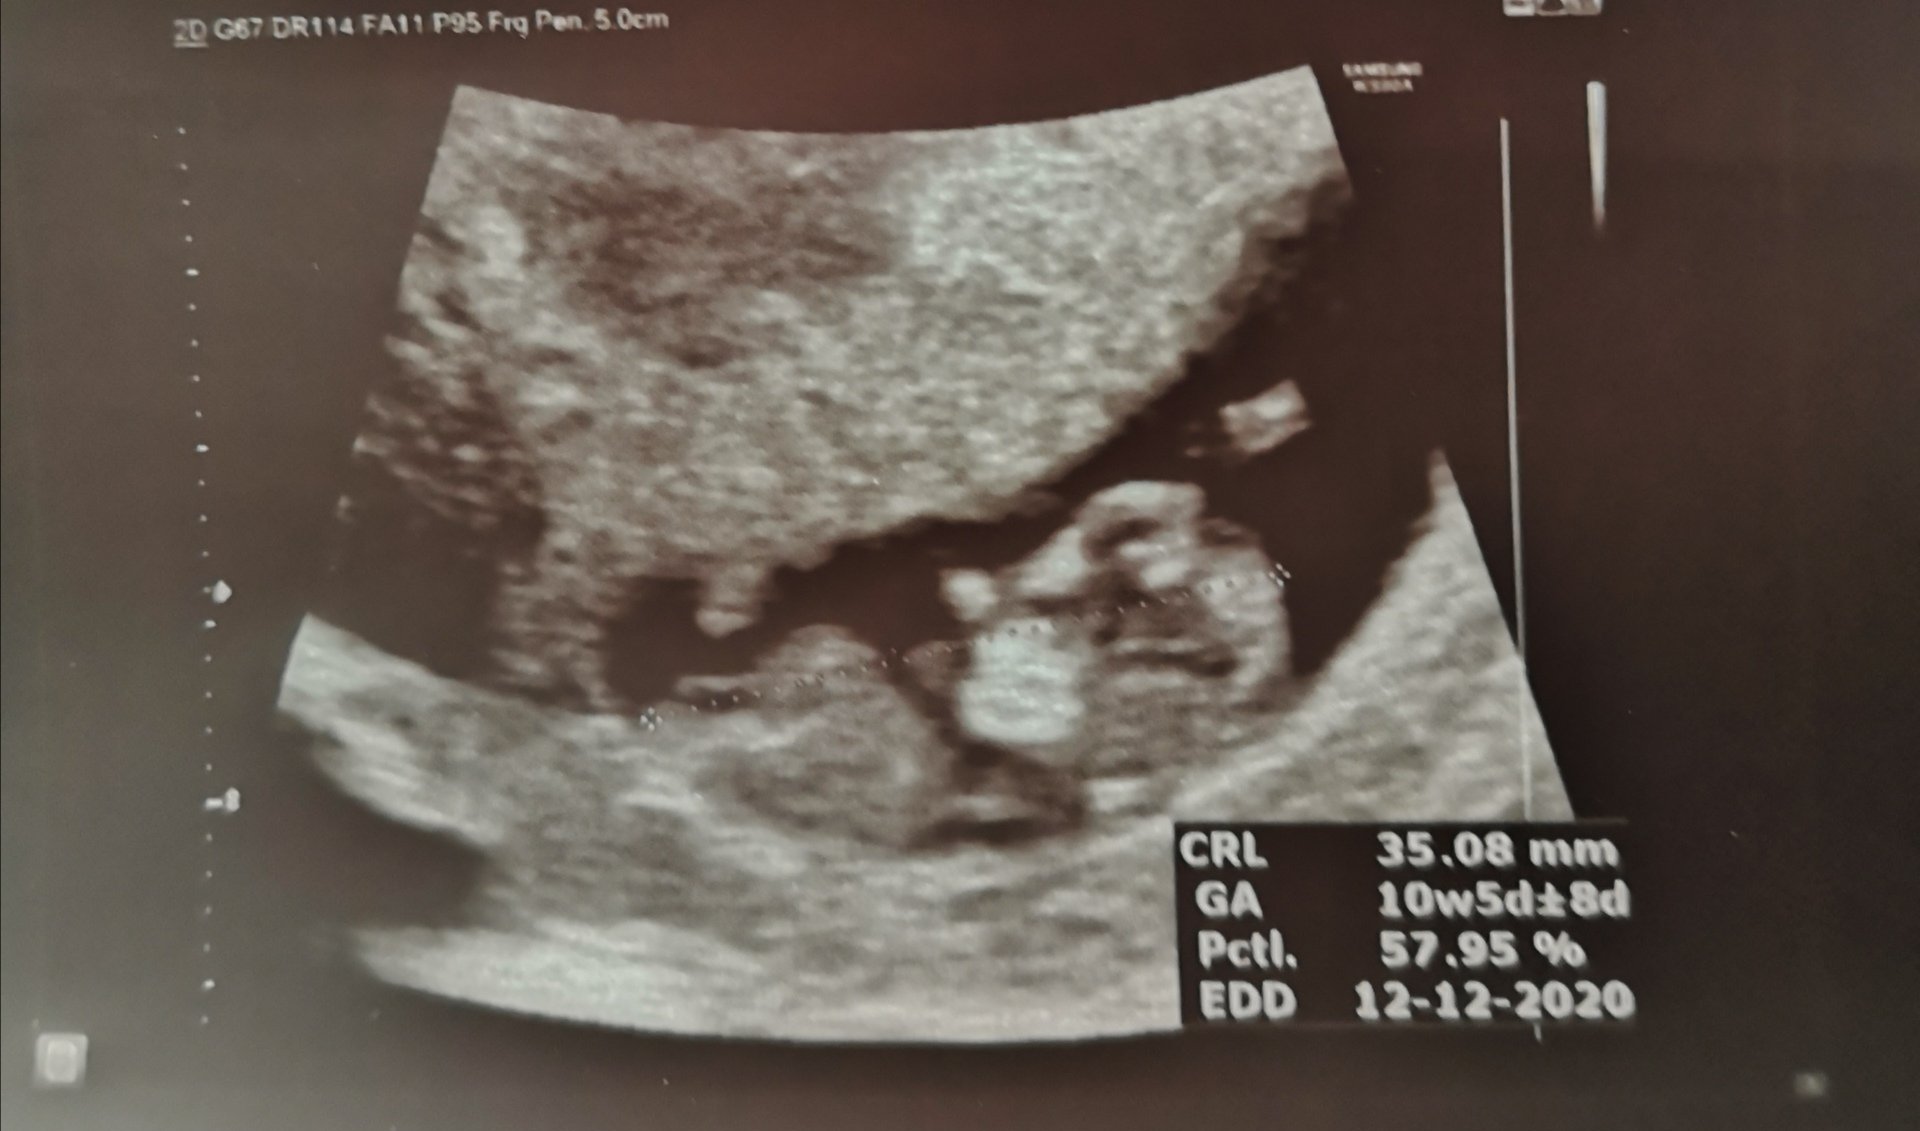

Туко що се връщам от преглед и всичко излежда наред. Малкото човече не спря да мърда. Пулса сега е 172, за което лекарката каза, че е много добре. Поне отлепянето вече се е оправило и ми записаха час за БХС за 05.06 (12г.с. + 4дни)

Здравейте момичета. Във вторник съм на последен преглед при др. Цветков във Надежда. Тогава ще съм 10+5. Предишната бременност бях при др. Михова на ЖК в Надежда, но сега тя е в майчинство. Избрах си докторката там, остава само да се запиша при нея. Моя приятелка работи в Надежда, бе с близнаци и тази лекарка я е спасила от руптура на матката. Каза,че била много добра. Като се запиша при нея ще ви кажа името.